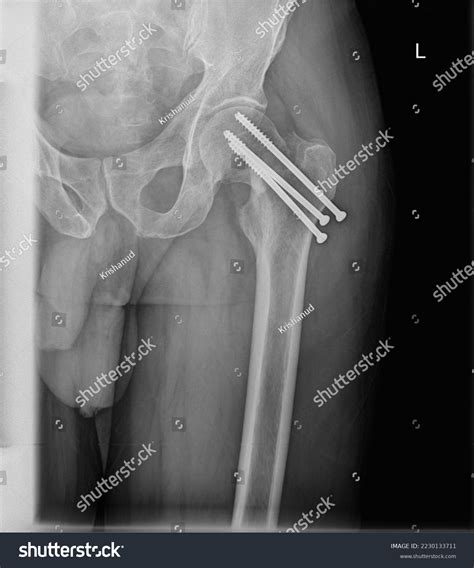

Conversely, surgical intervention is often required for displaced or compound fractures. Surgeons may perform Internal Fixation, where metal plates, screws, or rods are used to hold the bones in the correct position during the healing process. In cases of severe trauma, External Fixation—a frame attached to the outside of the leg—might be used temporarily to stabilize the area before a secondary surgery.